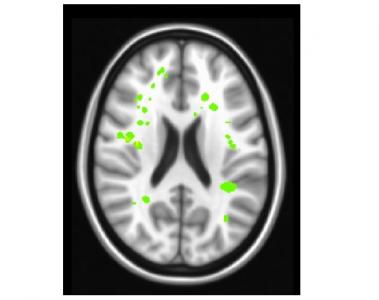

Les AVC silencieux (en vert clair sur visuel) ont aussi des effets débilitants sur la fonction exécutive, sur la capacité du cerveau à exécuter des tâches complexes nécessaires pour le maintien d'un travail ou la réussite scolaire. A priori, la cause de ces AVC peut paraître évidente, liée aux cellules sanguines endommagées et au manque d’oxygène du cerveau. Moins d'oxygène au cerveau entraîne bien l’AVC. Cependant, l’équipe montre ici que le volume total d'oxygène n’est pas vraiment réduit chez les patients atteints de drépanocytose : car le corps compense la teneur réduite en oxygène du sang en augmentant le flux sanguin vers le cerveau. Alors pourquoi ces patients souffrent-ils d’AVC ?

Une disparité en oxygène selon les zones du cerveau : une technique d'imagerie avancée permettant de mesurer le flux sanguin, révèle ainsi une disparité entre les zones du cerveau. Alors que l'apport total d'oxygène au cerveau reste inchangé, l'apport d'oxygène à la substance blanche est réduit de plus d'un tiers (35% en moyenne) chez les patients atteints. Or, c'est dans cette partie du cerveau que surviennent la majorité des accidents vasculaires cérébraux silencieux chez ces patients. Si la matière grise est composée de neurones, des cellules du cerveau qui stockent des informations, la substance blanche est le réseau que les neurones utilisent pour transmettre ces informations. Chez ces patients, le corps fait la différence entre matière grise et substance blanche, en donnant clairement la priorité aux neurones. Ce qui a du sens -écrivent les chercheurs- car garder les neurones en vie est essentiel à la survie. Un AVC dans la matière grise est catastrophique, un AVC silencieux dans la substance blanche ralentit « simplement » le traitement de l'information. Cependant certains AVC dans la substance blanche peuvent entraver considérablement certains aspects de la vie quotidienne du patient.